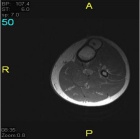

17 year old male c/o left shin pain. He is active in sports. First noted pain while running and with activities. Pain has been intermittent over 9 month period but more constant recently. A palpable lump is present on the left tibia which has not changed in size.